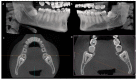

(1) Background: This study assessed the spatial position and anatomical features associated with impacted third molars through a map-reading strategy employing cone-beam computed tomography (CBCT). (2) Methods: The positioning of impacted third molars on CBCT was assessed using Winter's and Pell and Gregory's classifications. External root resorption in mandibular second molars was categorized according to Herman's classification. Additionally, the relationship between the mandibular third molar root apex and the mandibular canal was examined. Comparative statistical analysis was conducted using Fisher's exact test, with a significance level considered as 5%. (3) Results: The results indicated that, based on Winter's classification, 48.06 % of impacted teeth were positioned mesioangularly. Employing Pell and Gregory's classification, 43.22% of the impacted molars fell into positions B and C, with 54.2% classified as Class II. A notable 69.7% of teeth exhibited no contact between the root apex and the mandibular canal, and external root resorption in the distal aspect of the second molar was absent in 88.7% of cases. (4) Conclusions: Utilizing the map-reading strategy with CBCT scans to assess the anatomical positions and characteristics of impacted third molars enhances professional confidence and sets a standard for quality and safety in the surgical procedure for patients.